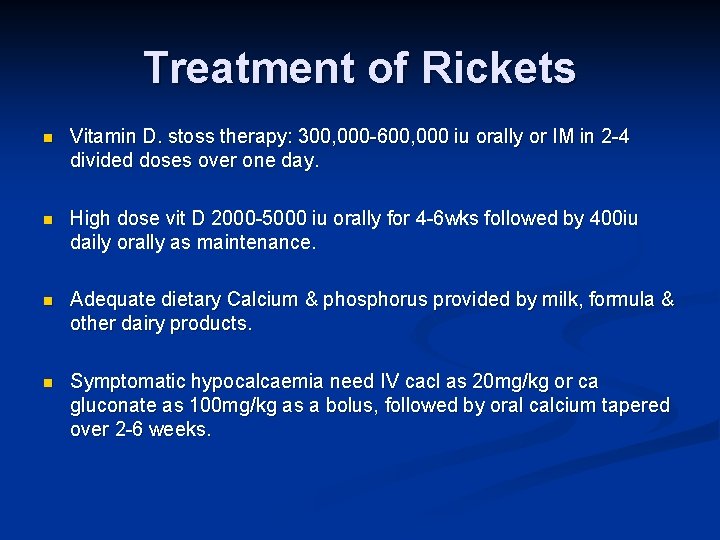

Treatment of Rickets n Vitamin D. stoss therapy: 300, 000 -600, 000 iu orally or IM in 2 -4 divided doses over one day. n High dose vit D 2000 -5000 iu orally for 4 -6 wks followed by 400 iu daily orally as maintenance. n Adequate dietary Calcium & phosphorus provided by milk, formula & other dairy products. n Symptomatic hypocalcaemia need IV cacl as 20 mg/kg or ca gluconate as 100 mg/kg as a bolus, followed by oral calcium tapered over 2 -6 weeks.